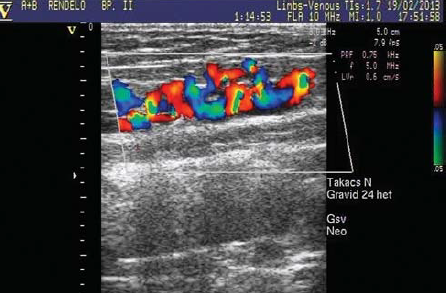

2. ábra.

A sapheno-femoralis junkció elzárása a v. femoralis szintjében.

A visszérműtét után, de még a terhesség előtt elvégzett UH vizsgálat minden esetben zárt junkciót és saphena törzset mutatott. A lézer fény hullámhosszának változása, vagyis a készülékek cseréje, a kezelt erek elhegesedésében változást nem okozott, az eredmény minden esetben megfelelő volt. Recidiv varicositast egyetlen esetben sem találtunk. A SFJ 26 végtagon a v. femoralis szintjében volt elzárva (68,4%) (2. ábra). Saphena csonkot 12 junkciónál (31.6%) észleltünk, amelyek hossza 7.5 ± 3.73 mm.